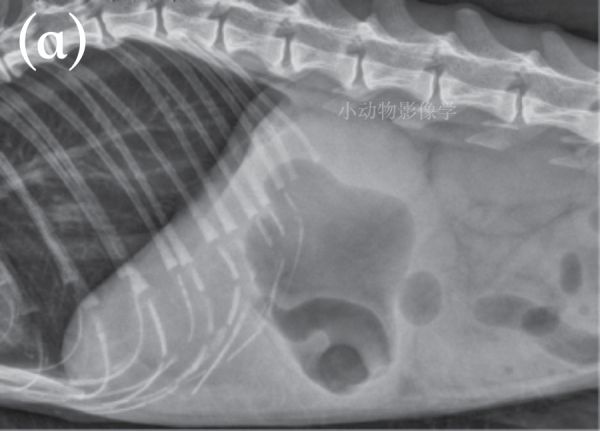

病例1.14岁猫功能性肠梗阻,进食异物后呕吐继发于电解质异常。入院时猫无反应,卧着。(a)左侧位。(b)腹背位。胃是被液体和气体膨胀的在超声检查中,胃(c)和小肠(d)有液体膨胀。(e)胃由于吞食空气,小肠也会膨胀并充满气体,如图所示,这只13岁的猫心脏疾病引起的呼吸窘迫。胸尾部可见胸腔积液(箭头)。